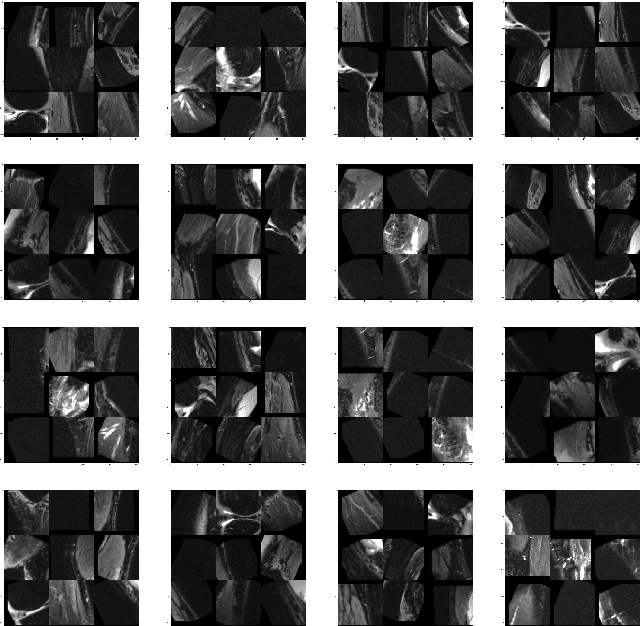

The success and efficiency of Deep Learning based models for computer vision applications require large scale human annotated data which are often expensive to generate. Self-supervised learning, a subset of unsupervised learning, handles this problem by learning meaningful features from unlabeled image or video data. In this paper, we propose a self-supervised learning approach to learn transferable features from MRI clips by enforcing the model to learn anatomical features. The pretext task models are designed to predict the correct ordering of the jumbled image patches that the MRI frames are divided into. To the best of our knowledge, none of the supervised learning models performing injury classification task from MRI frames, provide any explanations for the decisions made by the models, making our work the first of its kind on MRI data. Experiments on the pretext task show that this proposed approach enables the model to learn spatial context invariant features which helps in reliable and explainable performance in downstream tasks like classification of ACL tear injury from knee MRI. The efficiency of the novel Convolutional Neural Network proposed in this paper is reflected in the experimental results obtained in the downstream task.